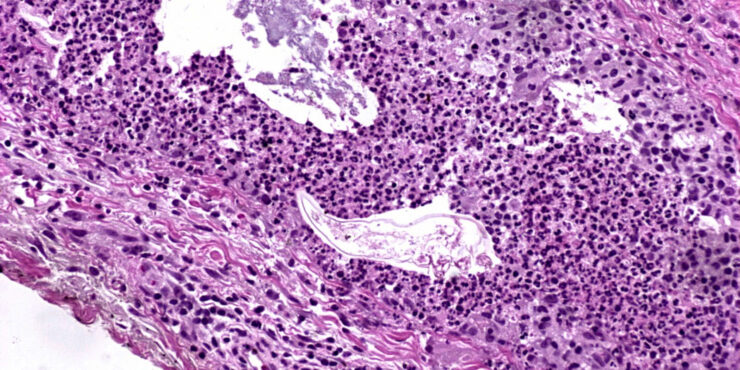

Darier =داء داريير Dariers Disease Darier’s disease is usually transmitted in an autosomal dominant pattern. It has been found to be due to mutations in the ATP2A2 gene on chromosome T2, which encodes the sarcoplasmic/endoplasmic reticulum calcium pumping ATPase SERCA2 (206). The gene is 12q23-24.1. In typical cases, there is a more or less […]